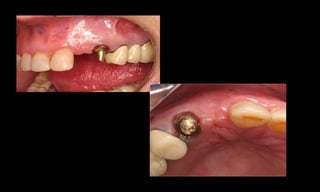

10-10-2005

Novembro de 2005

24-01-2006

Cone Morse